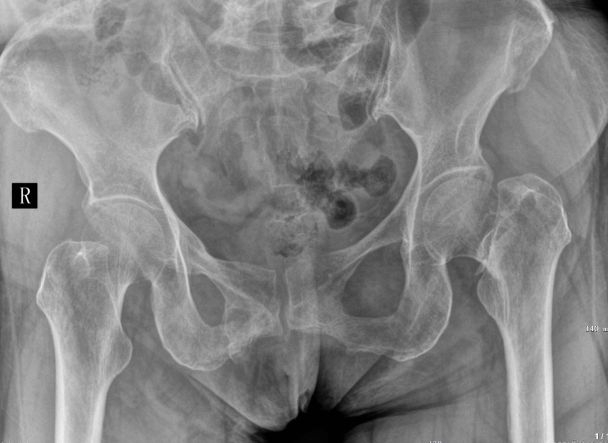

“在很多人的眼中,脑梗死显然是自身疾病引起的。其实不然,外伤也会导致出现脑梗死。”宁波诚和司法鉴定所副主任柴以辉说,在鉴定过程中,通过多次会诊及伤情和影像片前后比较,并经过全身体检,排除了王师傅自身脑血管疾病及脊髓、周围神经损伤引起脑梗死的可能性。最后,终于确认了王师傅的脑梗死属于少见的外伤性脑梗死,是因交通事故引起的。

至此,本案终于水落石出。法庭也根据该所出具的鉴定书,判定车主方和保险公司方赔偿王师傅40多万元。经过反复解释和沟通,事情终于得到圆满解决,王师傅也终于得到了相应的赔偿,并揭开了困扰自己两年的疑惑。